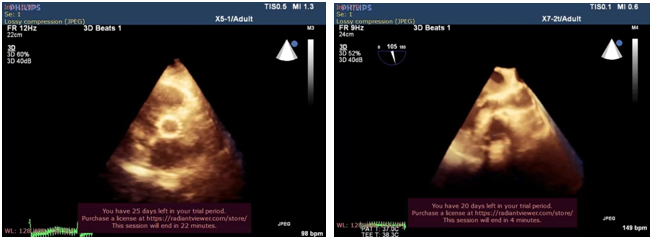

Ciddi aortal çatışmazlıqla bağlı kardiogen şok xəstədə TAVI